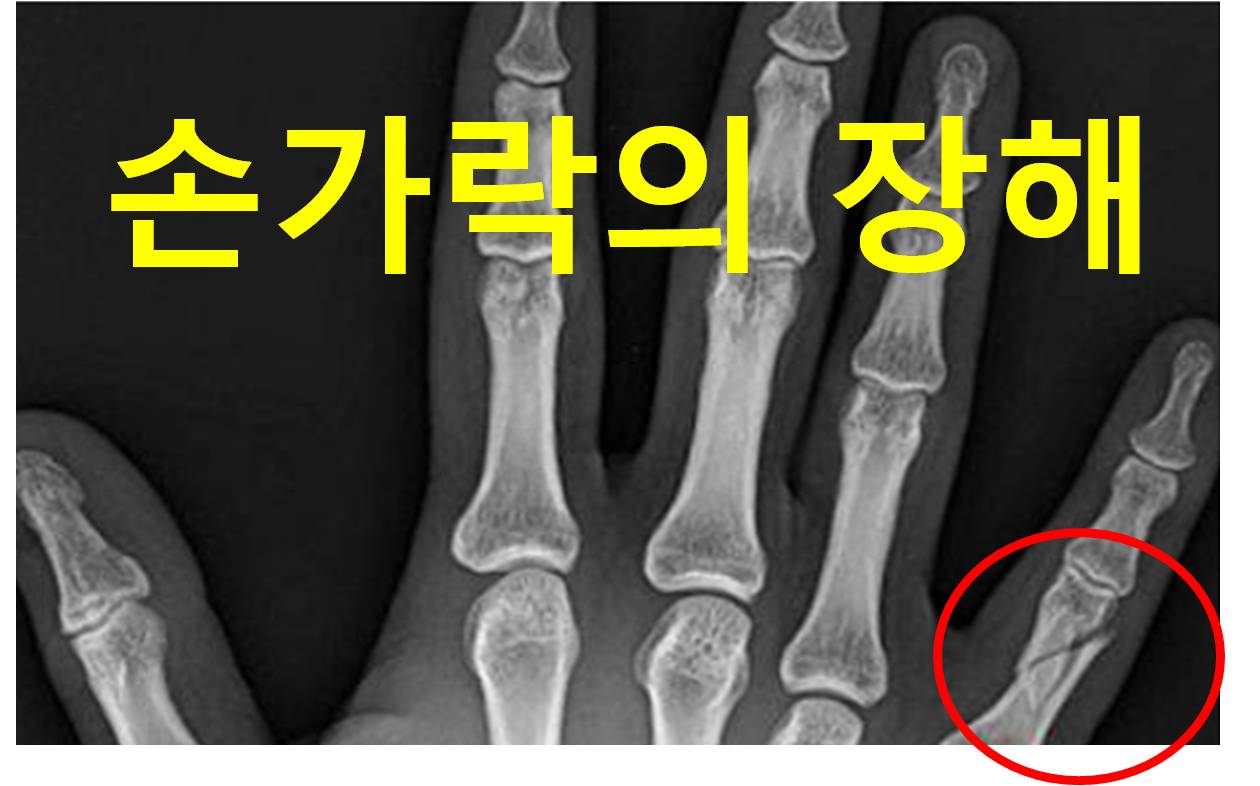

개인보험 후유장해는 총 13개 유형으로 구분하고 그 중 가장 마지막 유형이 신경계 정신행동 장해 입니다. 앞의 12개 항목의 장해는 신체 각 부위의 기능으로 평가하는 반면에, 13번째 신경계 정...